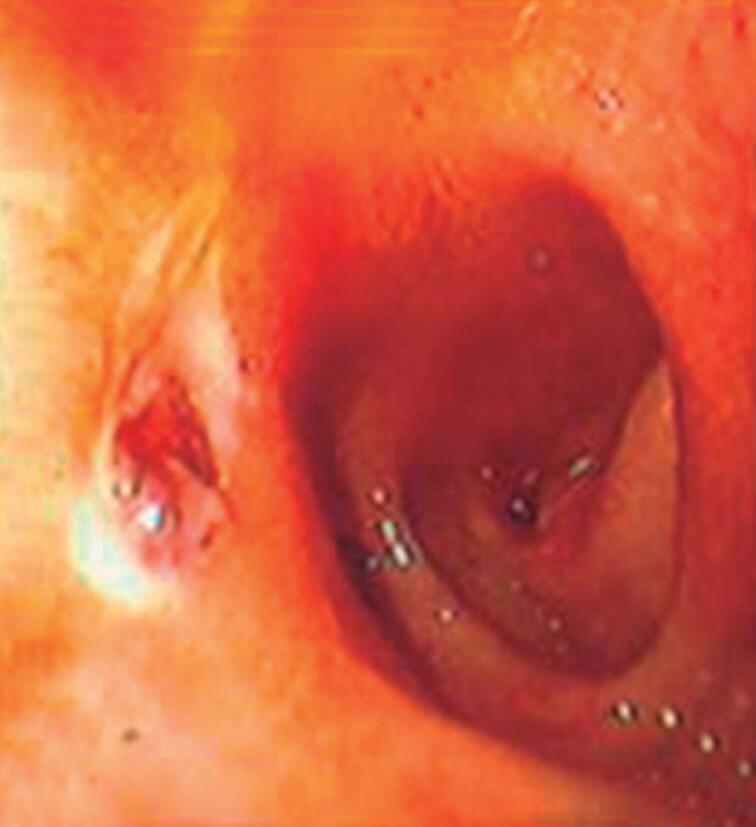

Fig. 2-31. Visão endoscópica de úlcera péptica gástrica (a,b); duodenal (c,d) com sangramento e substrato anatomopatológico do estômago com sangue e úlcera péptica (e,f). (Fonte: Arquivo do Departamento de Cirurgia-FCM/ unicamp.)